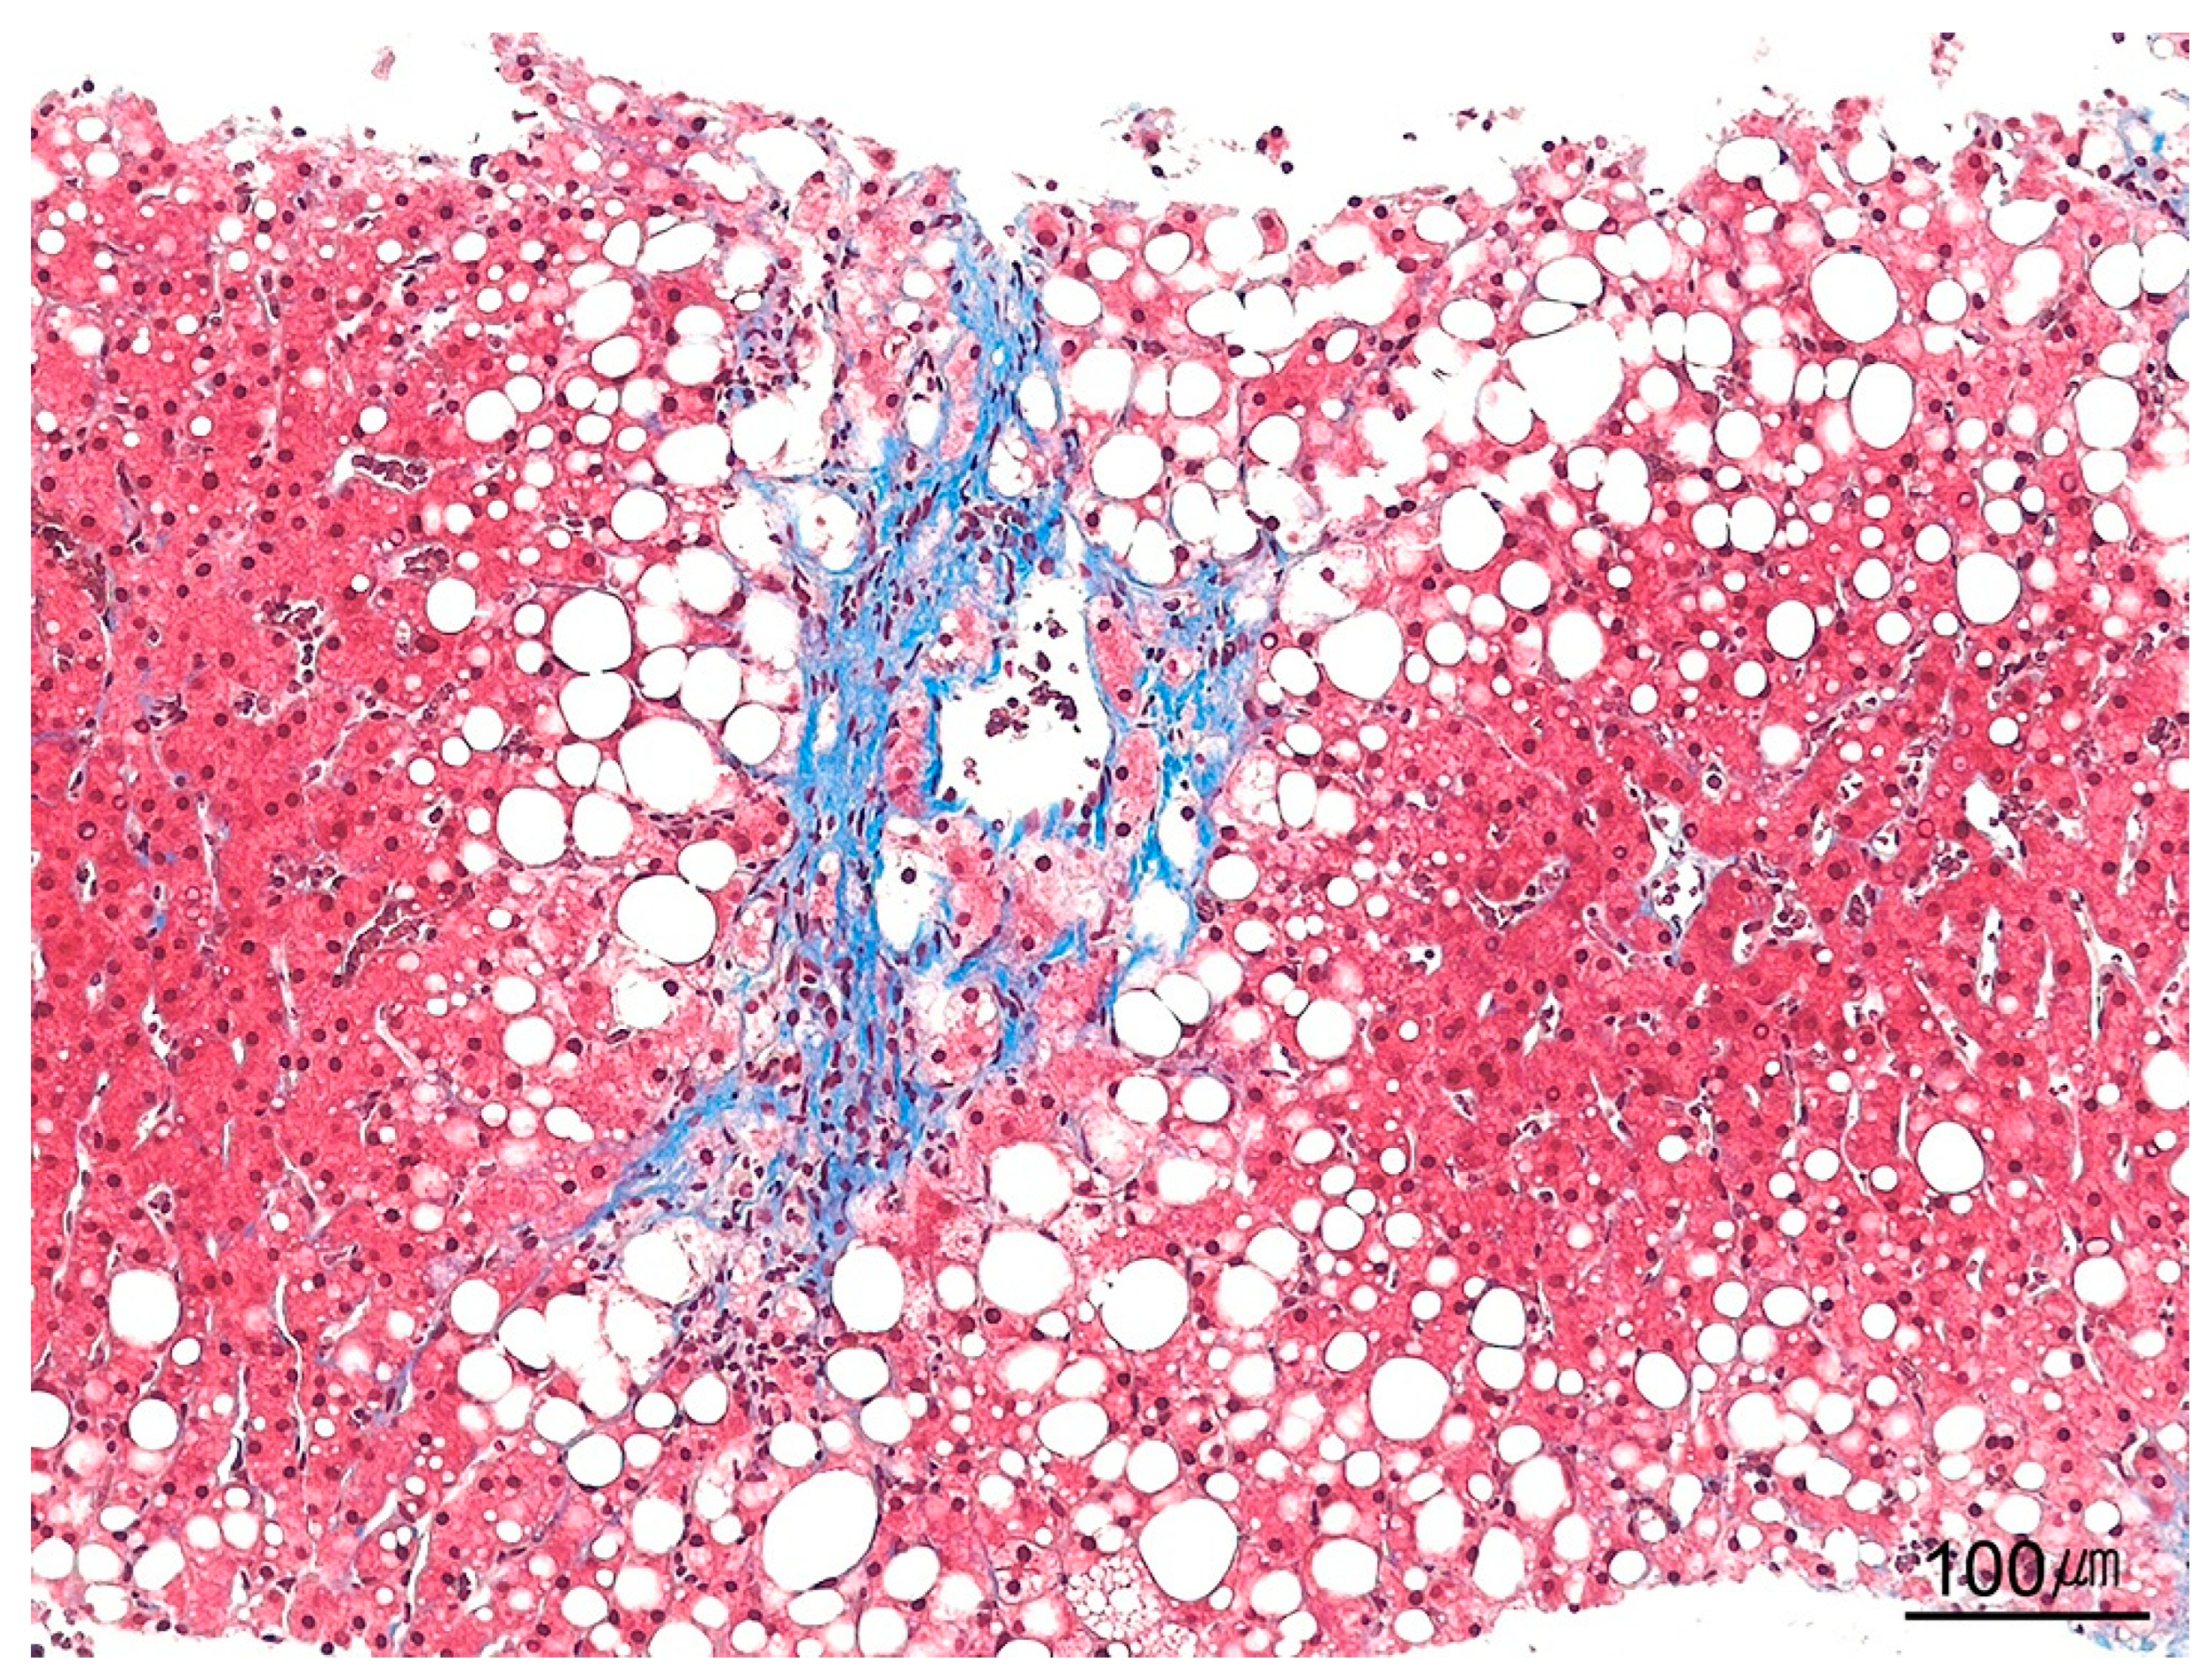

9.9.4. Bridging Fibrosis

9.9.5. Cirrhosis